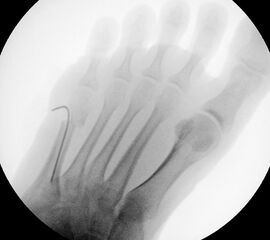

In der Regel bestehen aktive Wachstumsfugen bei Mädchen bis zum 12. und bei Jungen bis zum 14. Lebensjahr, mit Abweichungen von einem Jahr nach unten und nach oben. Präzise Informationen unter anderem darüber gibt das präoperative Röntgenbild (Abb. 2).

Abb. 2 a-c: offene Wachstumsfugen MT I Basis und Zehen (a), teilweise geöffnete Wachstumsfugen (b) und geschlossene Wachstumsfugen (c).

Zum Lesen der Bildbeschreibung und zur Vollansicht bitte die Bilder anklicken. Bilder: A. Helmers.

Die erforderlichen Osteotomien sind daher dem Fugenverlauf anzupassen, diese sind unbedingt zu respektieren. Wird eine Wachstumsfuge versehentlich mit der Fräse verletzt, kann durch partiellen oder kompletten Fugenverschluss ein Fehlwachstum provoziert werden. Achsabweichungen oder ein Wachstumstopp der betroffenen Region können die Folge sein. Offene Wachstumsfugen begrenzen die Osteotomieausrichtung besonders im Bereich des dorsalen Calcaneus, der Metatarsale I Basis und der IV. oder V. Zehe im End- und Mittelglied.